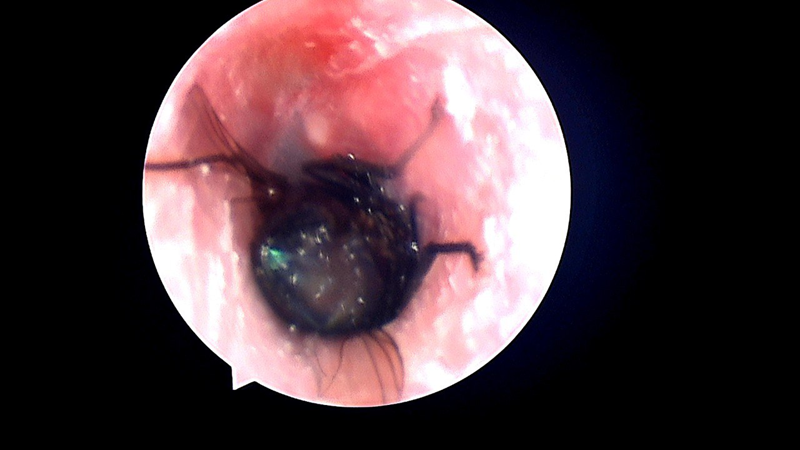

Qua thăm khám lâm sàng và nội soi tai mũi họng, bác sĩ phát hiện trong tai trái bệnh nhân có dị vật là côn trùng còn sống. Ngay lập tức, bác sĩ đã xịt thuốc gây tê làm bất động côn trùng, sau đó khéo léo sử dụng dụng cụ chuyên dụng gắp ra ngoài. Dị vật được xác định là một con ruồi trâu.

Hình ảnh nội soi cho thấy con ruồi trâu trong ống tai của người bệnh

Kết thúc thủ thuật, ống tai bệnh nhân nguyên vẹn, không chảy máu, không ảnh hưởng đến màng nhĩ, các mảnh vụn và dịch tiết của côn trùng được loại bỏ hoàn toàn.